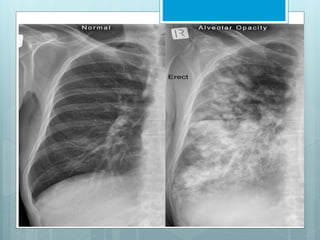

Radiological Features of

Consolidation

 Increased density.

 Acinar shadow.

 Silhouette sign.

 Air bronchogram.

Distribution of consolidation can vary widely.

 Can be described as “patchy”, “homogenous”, or

generalized”.

 Can be described as focal or by the lobe or segment

of lobe affected.